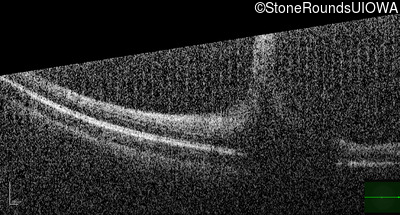

Optical Coherence Tomography - Right - 20/125

Exemplar